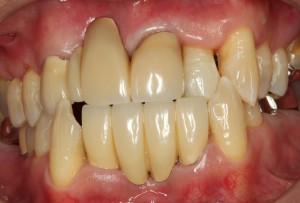

治療後の歯ぐき

きれいなピンク色の引き締まった歯ぐき

歯周病の治療を行い、噛み合わせを整えて、最終的なかぶせものでつなげて歯を守っています。

健康的な引き締まったピンク色の歯ぐきになっています。